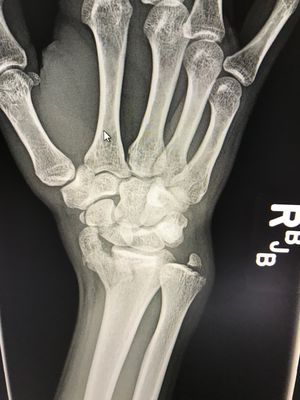

Intra-articular distal radius fracture with mild impaction and volarly displaced fracture fragment, also a comminuted scaphoid fracture extending through the waist as well as a minimally displaced scaphoid tubercle fracture fragment. Additionally mildly displaced ulnar styloid fracture fragment. All happened falling of a bicycle. Don’t forgot to wear helmets!